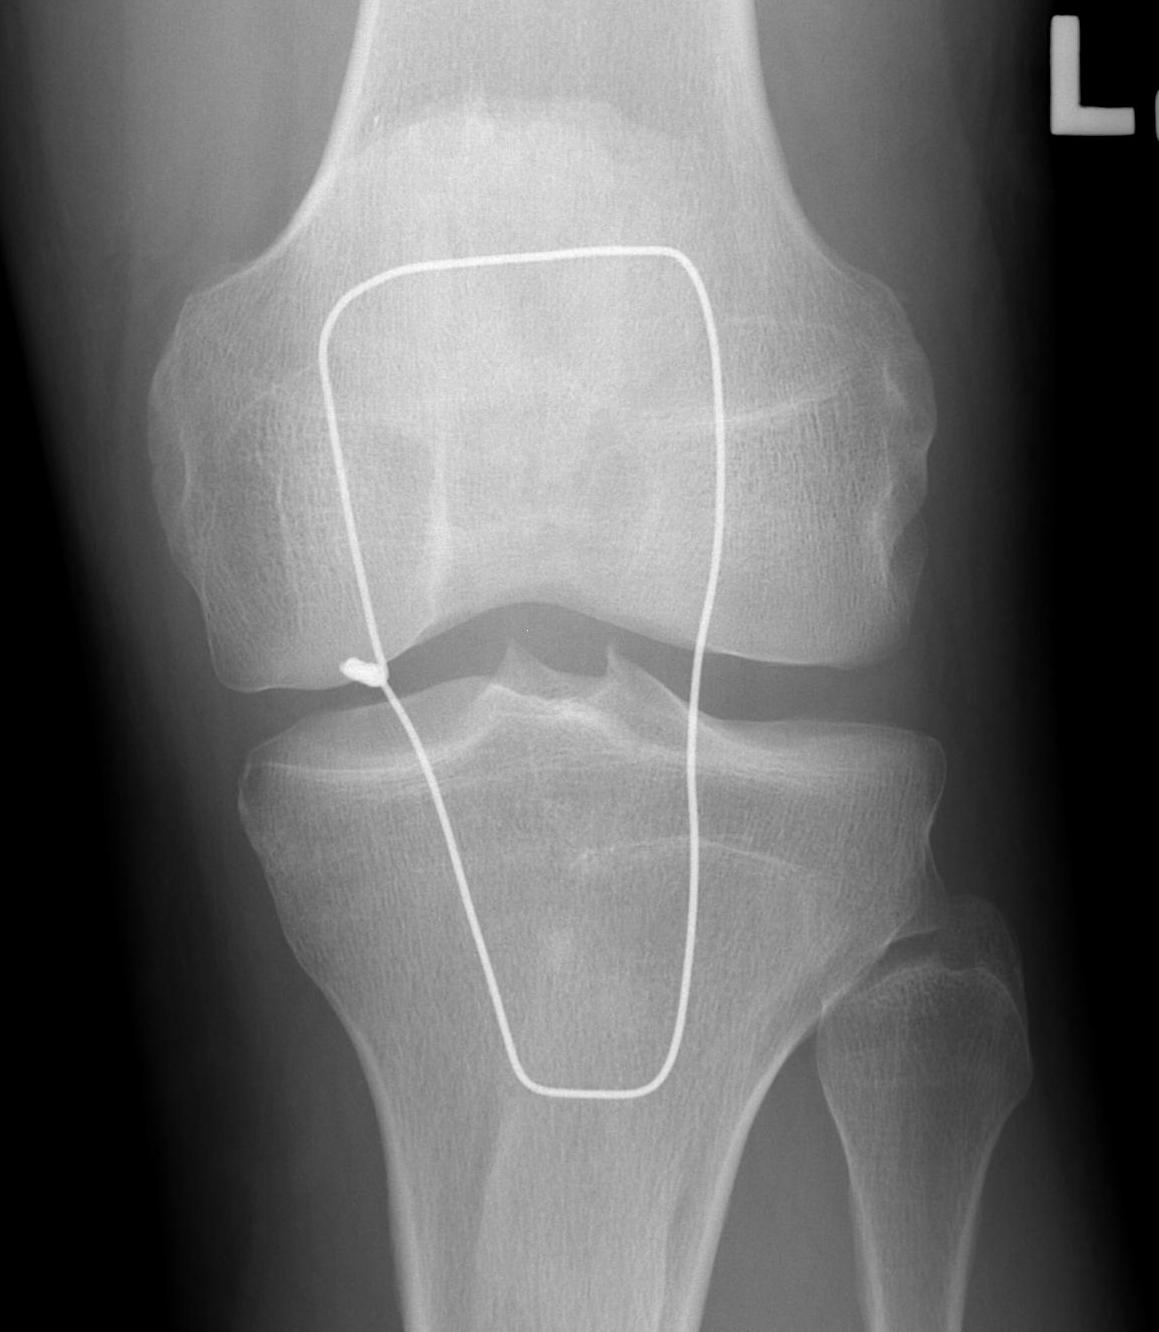

Xray

Patella alta / high riding patella

Distal Pole Patella Fracture

Can reinforce with box wire loop

- large gauge wire 18G

- drill hole in tibial tuberosity

- transverse drill hole in patella

- pass in square and tie

- protects patella tendon

- problem is will break / irritate / need removal

- only do if concerned re repair